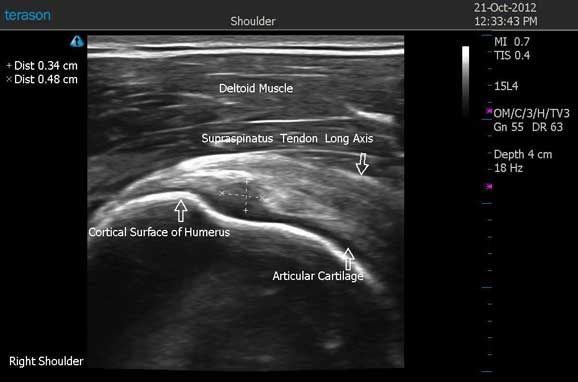

Figure 2 demonstrates a 0.34 cm x 0.48 cm hypoechoic defect on the articular side, with loss of the normal fibrillar pattern.